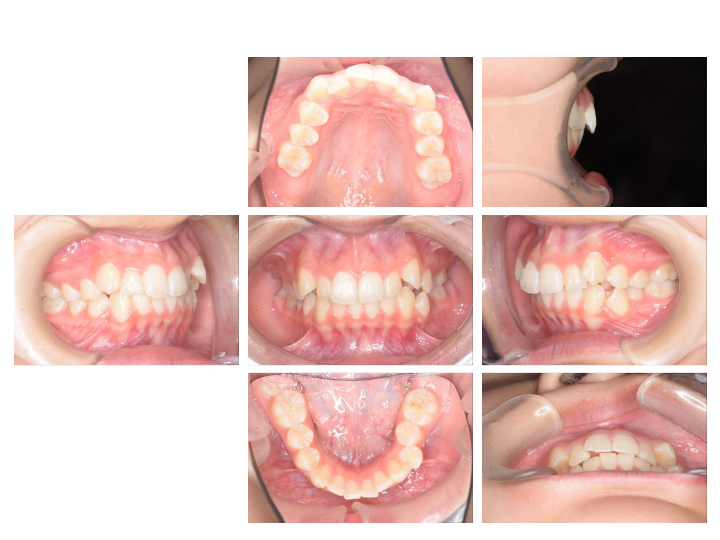

お子さんの矯正(小児矯正)は、あごの骨のバランスや大きさを整える「1期治療(骨格矯正)」と、永久歯が生えそろってから歯の位置を整える「2期治療(歯列矯正)」の2段階からなります。

乳歯と永久歯が混じった時期の治療で、主に成長を利用した治療を行ないます。(6~10歳)